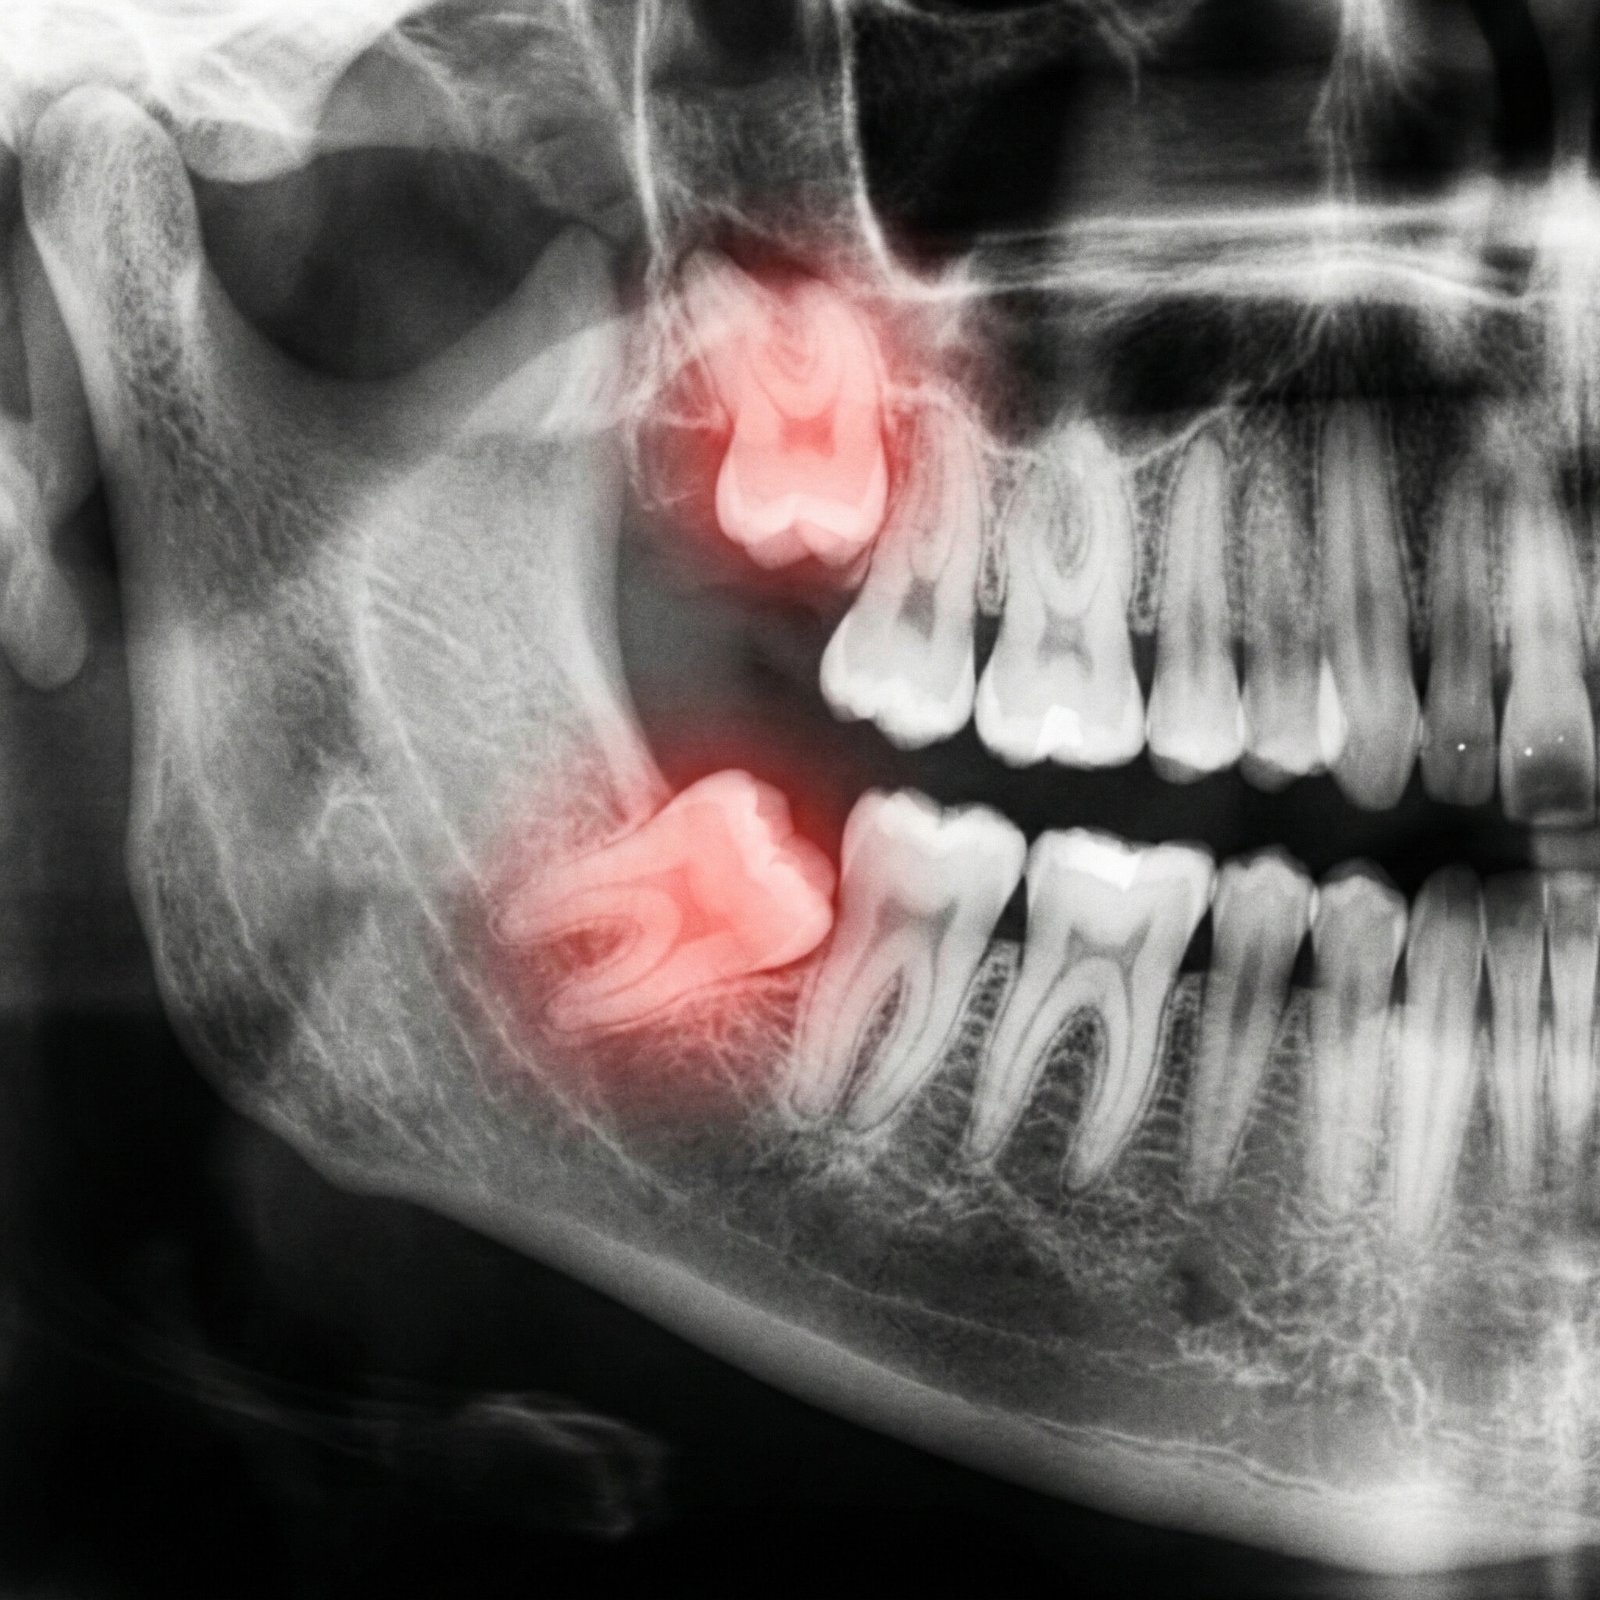

Traitez les problèmes de dents de sagesse grâce à nos extractions et soins spécialisés.

Traitez efficacement les problèmes de dents de sagesse grâce à nos extractions et soins spécialisés.